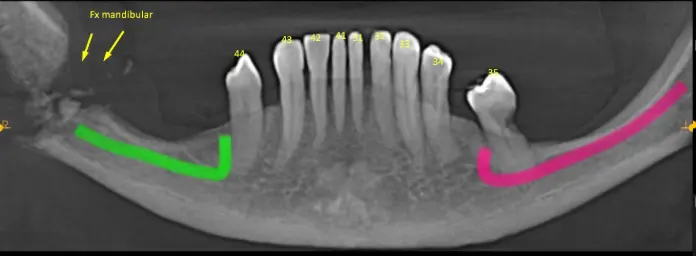

Tanto en la radiografía panorámica (imagen 1) como la tomografía maxilar inferior se puede observar una fractura mandibular a la altura del Angulo de la mandíbula con resto de fragmento óseo. (Fx Conminutas) Como también se logra ver todavía resto radicular de pieza dentaria. Ver imágenes 2 a imagen 5.